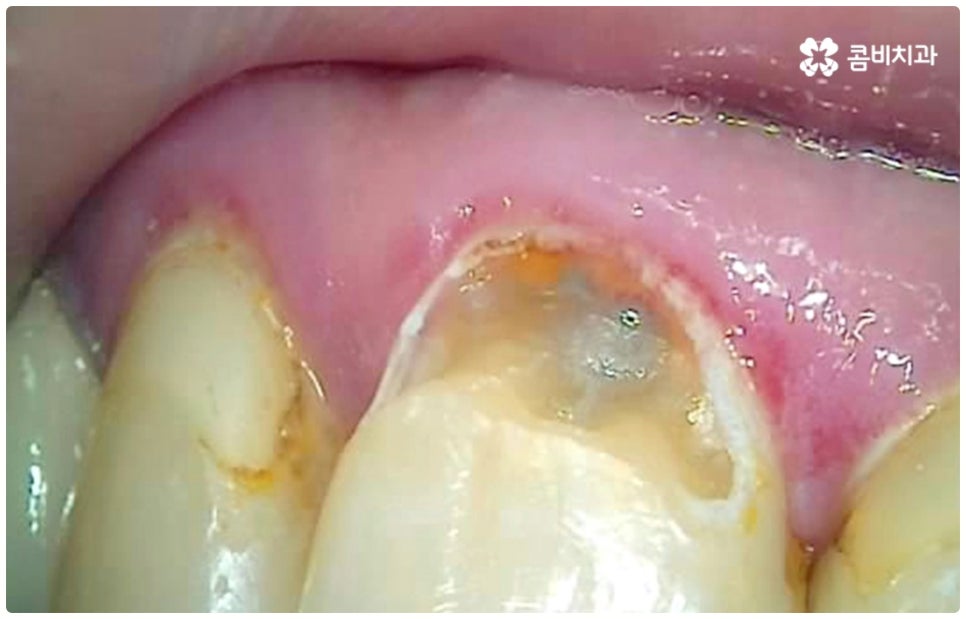

충치는 하루 아침에 생기는 것이 아니라 단계적으로 발전하는 구강 질환이며 시간이 지난다고해서 자연적으로 나아지지 않기 때문에 초기에 적절한 치료를 하지 않고 방치하게 되면 치아 손상이 점점 더 커지게 되고 결국 치아 상실까지 일으킬 수 있어 주의하실 필요가 있는데요. 충치를 초기에 발견하고 충치치료종류 중 레진으로 직접 때우는 치료를 하면 보다 빠르고 간편한데도 불구하고 대부분의 환자분들이 이 시기에 제대로 대처하지 못하는 이유는 충치가 처음 발병하는 치아의 가장 바깥쪽 겉면 (법랑질) 에는 신경이 없기 때문에 환자분들이 통증 등 이상 현상을 느끼지 못하는 경우가 많고 또한 겉으로 보기에도 초기에는 충치로 인한 치아의 색상이나 모양 변화가 뚜렷하지 않아 놓칠 가능성이 높기 때문일 거예요. 초기에는 흔히 알고 계시는 충치 증상처럼 치아 일부가 검게 벌레먹은 듯 보이거나 치아 형태가 조금씩 무너지면서 구멍이 뚫린 것처럼 되지 않고 작고 불투명한 흰 점 또는 옅은 갈색 줄이 생긴 것처럼 느껴지기 때문에 알아차리기 힘들며 그마저도 육안으로 확인하기 어려운 곳 (구강 안쪽이나 치아 사이, 보철물 안쪽) 이라면 발견조차 못할 수 있어요.

그렇기 때문에 많은 분들이 일반적으로 시린 통증을 느낄 때 치과를 방문하게 되는데, 이 때는 이미 충치균이 치아의 단단한 겉면인 법랑질을 뚫고 상아질까지 침투한 단계일 가능성이 높으니 더 늦기 전에 바로 필요한 처치를 해 주실 필요가 있습니다. 상황에 따라 다르지만 보통 이 단계에서는 레진으로 직접 때워주는 치료가 적합하지 않은 경우가 많기 때문에 그럴 때는 충치치료종류 중 인레이 온레이와 같은 보철물을 이용하여 도움을 받을 수 있는데요. 이러한 치료는 손상된 부위를 깔끔하게 삭제한 후에 그 범위와 정도에 따라 빈 공간에 맞춤 제작한 보철물을 채워넣는 것으로 (인레이는 상대적으로 깊고 좁은 부위에, 온레이는 교두를 포함한 좀 더 넓은 부위에 적용), 재질 역시 다양한 가운데 치아의 위치 및 역할, 그리고 환자분들의 경제적 상황 등 여러 가지를 고려하여 가장 잘 맞는 것으로 선택하면 되니 꼼꼼한 검진 후 담당의 선생님과 각 재질의 장단점에 대해 사전 상담을 충분하게 해 보시고 신중한 결정을 내리시길 권유드리고 있어요.

만약 이 단계를 지나 더 오랫동안 충치를 방치하여 세균이 치아 내부 신경 조직이 분포하는 치수에 도달하게 되면 가만히 있어도 욱신거리는 극심한 통증을 느낄 수 있는데요. 이 때는 충치치료종류 중 근관(신경) 치료를 해 줄 필요가 있으며 변성된 신경을 제거하고 남아 있는 자연 치아를 보호하여 저작 기능을 제대로 수행할 수 있도록 하기 위해서는 크라운 치료를 통해 전체를 덮어씌워 줄 필요가 있습니다.